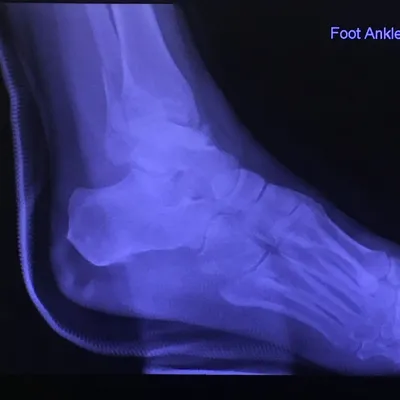

Pre-operative x-rays of the flatfoot with the talus deviated medially due to subluxing off the calcaneus causing the midtarsal joint to sublux laterally and uncovering of the talar head at the talo-navicular joint (left). The talus bone should line up with or be close to paralletl with a line drawn through the 1st metatarsal shaft (right). This is referred to as Meary's angle.

One case see an improvement in Meary's angle after surgical repair of the flatfoot with a subtalar joint implant which blocks the subluxation of the talus off of the calcaneus.